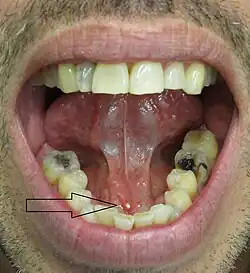

- Palpable hard lump, if the stone is located near the end of the duct.[1][3] If the stone is near the submandibular duct orifice, the lump may be felt under the tongue.

- Erythema (redness) of the floor of the mouth (infection).[3]

- Pus discharging from the duct (infection).[3]

- In advanced cases, a fistula may form to the skin of the neck or cheek.[5] See adjacent image demonstrating cutaneous fistulization.